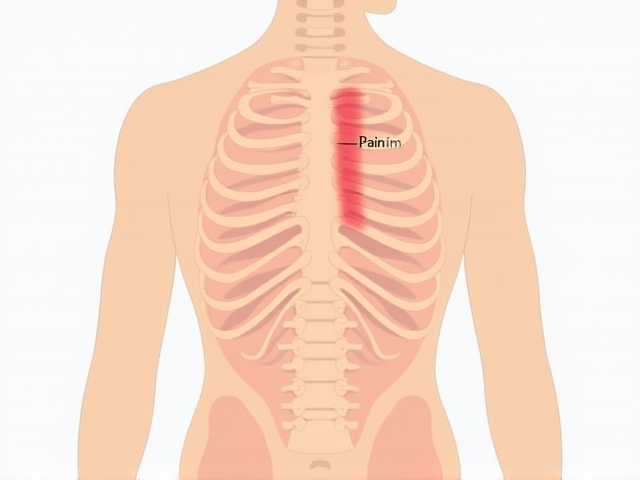

왼쪽 등과 갈비뼈 위의 통증 원인과 대처 방법

왼쪽 등과 갈비뼈 위의 통증은 다양한 원인으로 발생할 수 있으며, 이를 이해하고 대처하는 방법이 중요합니다. 이 포스트에서는 통증의 일반적인 원인, 진단 방법, 그리고 통증 완화를 위한 다양한 대처 방법에 대해 알아보겠습니다.

왼쪽 등과 갈비뼈 위의 통증의 일반적인 원인

왼쪽 등과 갈비뼈 위의 통증은 여러 원인으로 인해 발생할 수 있습니다. 주요 원인은 다음과 같습니다:

- 근육 긴장: 잘못된 자세나 과도한 신체 활동으로 인한 근육 긴장은 통증의 흔한 원인입니다.

- 신경통증: 신경이 압박받거나 염증이 생기면 통증이 발생할 수 있습니다. 이는 좌골신경통과 비슷한 형태로 나타날 수 있습니다.

- 갈비뼈 손상: 외부 충격이나 강한 기침 등으로 갈비뼈가 다칠 경우 통증이 발생할 수 있습니다.

- 내과적 원인: 심장 문제, 폐 질환, 위장 문제 등 여러 내과적 원인이 통증으로 나타날 수 있습니다. 특히 심장 질환의 경우 조기 발견이 중요한 만큼 주의가 필요합니다.